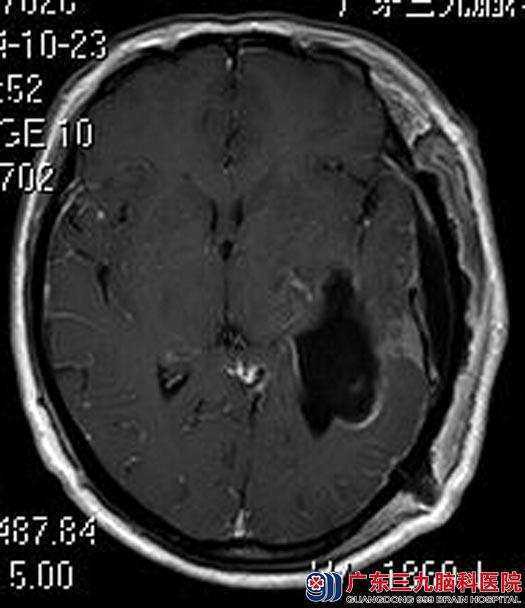

入住广东三九脑科医院综合神经外科,头颅MR检查提示:左侧颞叶区小脑天幕上方示一巨大不规则团块状肿块影,大小约为8.1cm×5.1cm×5.9cm;头颅CTA检查提示肿瘤血供极其丰富,左侧大脑中、后动脉受压移位。

脑膜瘤是颅内常见的良性肿瘤,对药物和放射治疗均不敏感,手术切除是可供选择的方法。完善相关检查后,由鲁明主任主刀,在全麻下行左侧小脑幕山巨大脑膜瘤切除术,术中显微镜下见淡红色肿瘤组织,质韧,血供丰富,予电磁刀全切肿瘤。术后,朱女士恢复很好,已康复出院。术后病理结果:脑膜瘤。